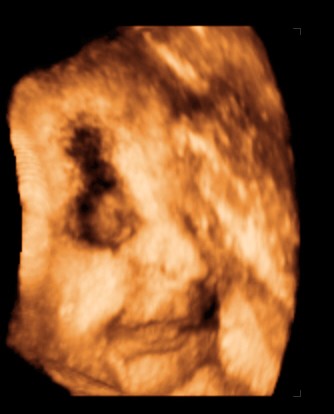

Moncsi, ha nem haragszol én is szeretnék inkognitóban maradni! Majd a babácskámról teszek képet a gmailre, ha megszuletik! Sajnos az UH képet azóta sem sikerult bescannelnem, pedig próbáltam, valamiért nem kommunikál a notebookommal a scaner, úgyhogy az UH tablóból mi kimaradunk!